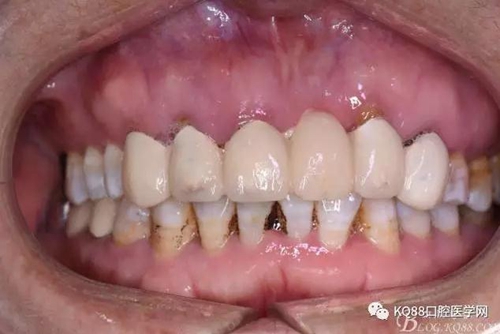

患者、王xx、女、56歲。主訴:右側(cè)上顎部反復(fù)腫痛兩年。??茩z查:上半口烤瓷橋修復(fù),12腭側(cè)隆起,捫診有輕微觸痛。X光:12根尖有圓形規(guī)則陰影,范圍月、約1.0x1.2cm,邊界清晰,11、12根管治療不完善。診斷:12根尖囊腫。治療計劃:1.行11、12根管治療術(shù)。2.擇期行根尖手術(shù)?;颊咄庵委煼桨?,簽知情同意書。

圖3.術(shù)前口內(nèi)正面照:12前庭溝輕度捫痛、有乒乓感